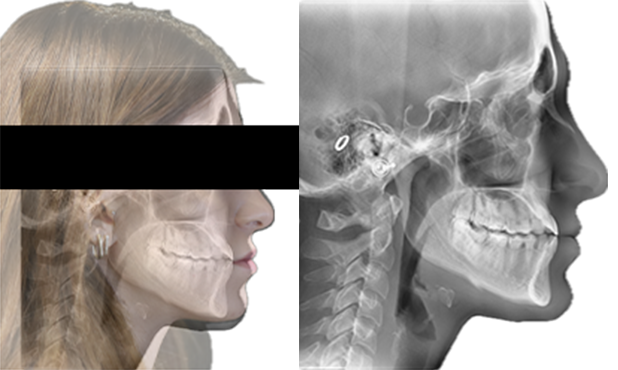

A 22-year-old female patient presented with a Class III malocclusion. She does not like her own profile. Her facial profile was straight with a slightly retrusive maxilla, the upper incisors were within normal inclination, and the lower incisors were retroclined. Bolton discrepency is on mandible for 6 teeth. A retruded upper lip and a normally positioned lower lip were noted. There was also a marked lack of midface support, and the constricted dental arches resulted in a narrow smile and pronounced dark buccal corridors.

Dr. OK regularly teaches biomechanics to postgraduate orthodontic students and has a solid background in the torque philosophy of the Damon Ultima™ system, and this case allowed him to further refine and illustrate that approach in a clinical setting.